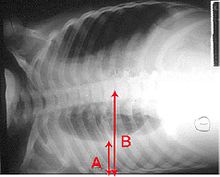

In pneumonia, a collection of fluid may form in the space that surrounds the lung. Occasionally, microorganisms will infect this fluid, causing an empyema. To distinguish an empyema from the more common simple parapneumonic effusion, the fluid may be collected with a needle ( thoracentesis), and examined. If this shows evidence of empyema, complete drainage of the fluid is necessary, often requiring a drainage catheter. In severe cases of empyema, surgery may be needed. If the infected fluid is not drained, the infection may persist, because antibiotics do not penetrate well into the pleural cavity. If the fluid is sterile, it needs to be drained only if it is causing symptoms or remains unresolved.

Rarely, bacteria in the lung will form a pocket of infected fluid called a lung abscess. Lung abscesses can usually be seen with a chest X-ray but frequently require a chest CT scan to confirm the diagnosis. Abscesses typically occur in aspiration pneumonia, and often contain several types of bacteria. Long term antibiotics are usually adequate to treat a lung abscess, but sometimes the abscess must be drained by a surgeon or radiologist.